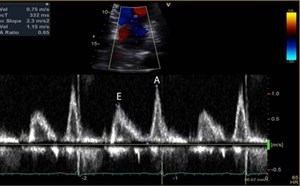

Join your colleagues and get your Ultrasound Program accredited. This accreditation system promotes the goals of quality, patient safety, communication, responsibility, and clarity regarding the use o...